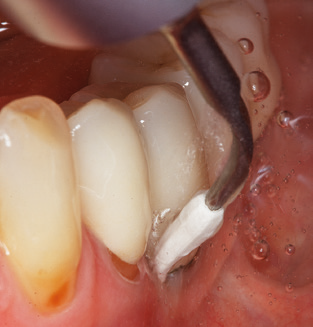

Following machine cleaning of the tooth and implant surfaces, the surfaces of the natural teeth are cleaned manually using standard hand instruments. When performing manual cleaning, particular attention must be given to maintaining the correct angle of application, appropriate sharpness, good support and working with the curette from apical to coronal. Either titanium or carbon curettes should be used for post-cleaning of the implant structures (Fig. 8). In addition to the use of ultrasonic devices, power jet devices can also be used in conservative dentistry. However, it must be taken into consideration that these procedures are not suitable for removing hard deposits and thus they cannot replace the use of hand instruments and ultrasonic instruments completely. In all cases, cleaning is followed by mechanical polishing of the accessible tooth and implant surfaces with polishing cups and polishing compounds (Fig. 9).

Fig. 4: Flexible probes with millimetre markings are recommended for the probing of dental implants (e.g. Colorvue Kit PCV11KIT6, Hu­Friedy). – Fig. 5a and b: A straight working tip (1P, W&H Dentalwerk Bürmoos GmbH) is a suitable instrument for use on all natural teeth. – Fig. 6: Curved working tips (3Pr/3Pl, W&H Dentalwerk Bürmoos GmbH) lend themselves to the processing of difficult-to-reach areas of the tooth and root surfaces (e.g. furcations). – Fig. 7: The tapered, hexagonal implant cleaning tip (1I, W&H Dentalwerk Bürmoos GmbH) permits atraumatic and efficient cleaning of the crown and abutment surfaces. – Fig. 8: Titanium and carbon curettes are suitable instruments for the manual cleaning of the implant surfaces.